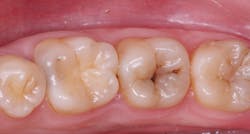

This is a well-known procedure, but it’s often confused with liners or bases. I have observed that almost all restorative dentists provide indirect pulp capping for their patients. The size and location of the dental pulp varies significantly depending on patient age and the extent of previous restorative treatment causing pulp response and reduction in pulp size (figure 1). When excavating caries, the ideal goal is to remove all observable caries without exposing the pulp. Often, the following situations occur in a typical day of practice: removal of the soft caries, dentin is hard to remove with an excavator, stained tooth structure remains, and the operator’s knowledge of dental anatomy and a radiograph indicate that a pulp exposure will occur if excavation is continued. An indirect pulp cap is placed on the deepest portions of the tooth preparation (figure 2).

A direct pulp cap is performed when the pulp is exposed during caries excavation, and it’s bleeding. The various definitions of when and if to do a direct pulp cap are extremely variable. Based on hundreds of direct pulp caps with impressive success, these are my criteria for performing a direct pulp cap (figure 3):